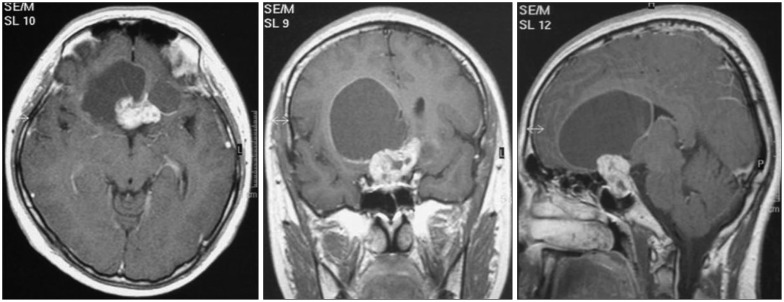

该研究包括53名男性和29名女性患者(男女比例=1.83:1),年龄中位数为42岁(15-79岁)。平均随访时间46个月(范围5-169个月)。其共同症状为视力障碍(50例;61.0%)、头痛(33例;40.2%)、精神疾病(10例;12.2%)、垂体功能减退(9例;11.0%)、全身无力(7例;8.5%)、癫痫(2例;2.4%)、意识丧失(2例;2.4%)和偶然感觉(2例;2.4%)。肿瘤的中等直径是3.0厘米(范围是1.5-7.0厘米)。核磁共振图像中,18%的肿瘤是纯肿瘤或者主要是实体瘤,20.5%是囊性肿瘤,61.5%是混合肿瘤。其中57例发生钙化(73.1%),20例发生阻塞性脑积水(24.7%)。有68个病人(82.9%)参与了三脑室。前额叶和后颅窝均有肿块扩大3例。

结果:GTR达到71例(86.6%),NTR达到7例(8.5%),STR达到3例(3.7%)。有一位病人被插入Ommaya储液槽并接受囊肿抽吸治疗。NTR和STR两组患者在11例残留肿瘤中,分别接受了立体定向放射外科治疗和放射治疗作为辅助治疗。有9例病人未接受任何辅助治疗。在年龄(p=0.791)、性别(p=0.312)、肿瘤大小(p=0.732)、下丘脑受累(p=0.345)等方面,GTR组与对照组的相关性无统计学差异。组织病理学分型(p=0.545)和脑积水(p=0.438)。但非GTR组全部肿瘤均出现钙化,各组间钙化程度有性差异(p=0.029)。